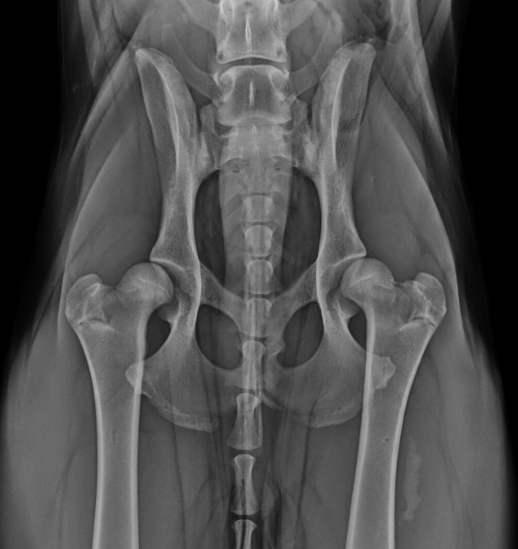

To confirm the diagnosis of hip dysplasia radiographs (x-rays) are required, which allow quantification of the degree of laxity within each hip as well as assessment for secondary osteoarthritic changes.